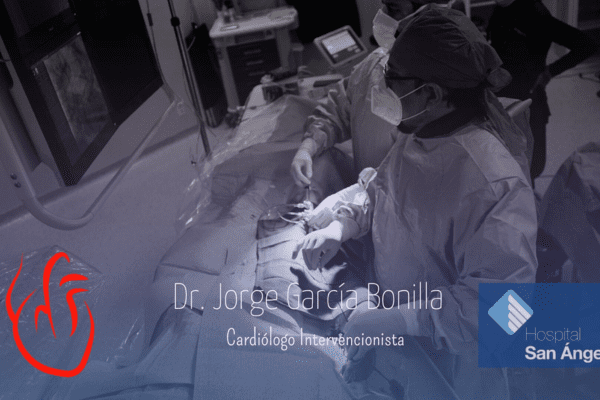

Dr. Jorge García Bonilla

Cardiología intervencionista en CDMX

El Dr. García Bonilla es un prestigioso cardiólogo intervencionista con amplios años de experiencia. Se especializa en enfermedades cardiovasculares, trastornos del ritmo cardíaco, enfermedades de la válvula cardíaca, e insuficiencia cardíaca.

Nuestros servicios están diseñados para brindarte un enfoque personalizado

Conoce mis instalaciones y algunos casos de pacientes en mi